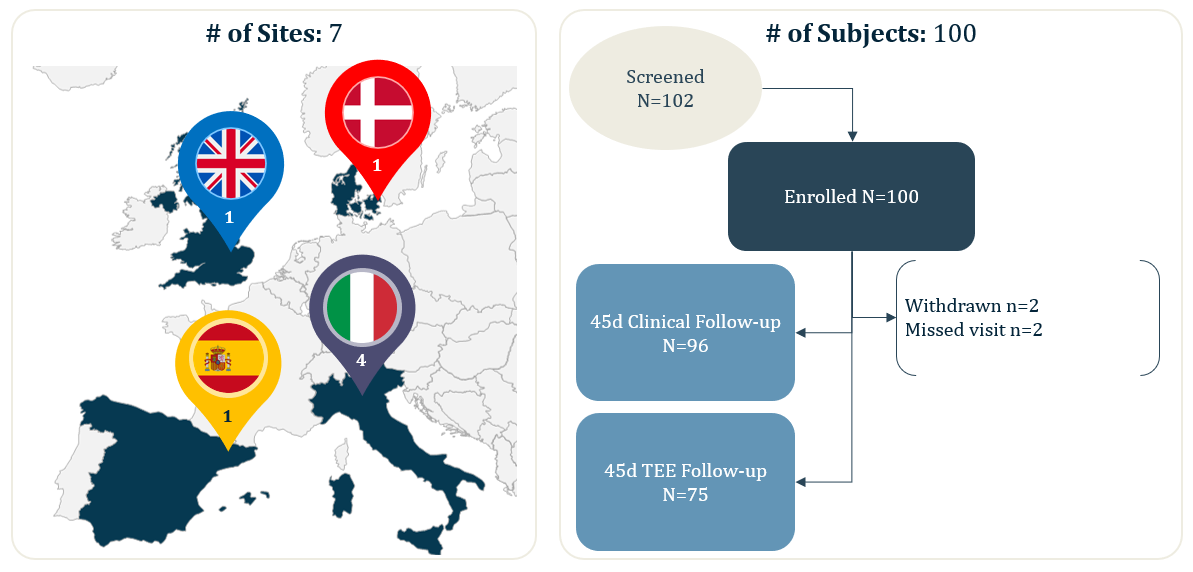

ICE LAA is a multi-center study with core-laboratory adjudication, this analysis reported the 45-days results from 100 real-world WATCHMAN FLX patients from 7 European centers.

- 100 real-world, European WATCHMAN FLX patients (from 7 implanting centers)

Outcomes with WATCHMAN FLX using Intracardiac Imaging: Results from ICE LAA

Jens Erik Nielsen-Kudsk

Aarhus University Hospital,

Aarhus, Denmark

Sergio Berti

Fondazione Toscana Gabriele Monasterio

Massa, Italy

Francesco Caprioglio

Ospedale San Bortolo

Vicenza, Italy

Frederico Ronco

Ospedale Dell Angelo

Mestre, Italy

Dabit Arzamendi

Hospital De La Santa Creu I Sant Pau

Barcelona, Spain

Timothy Betts

John Radcliffe Hospital

Oxford, UK

Claudio Tondo

Centro Cardiologico Monzino

Milan, Italy

Study Type: Prospective, non-randomized, single-arm, multi-center